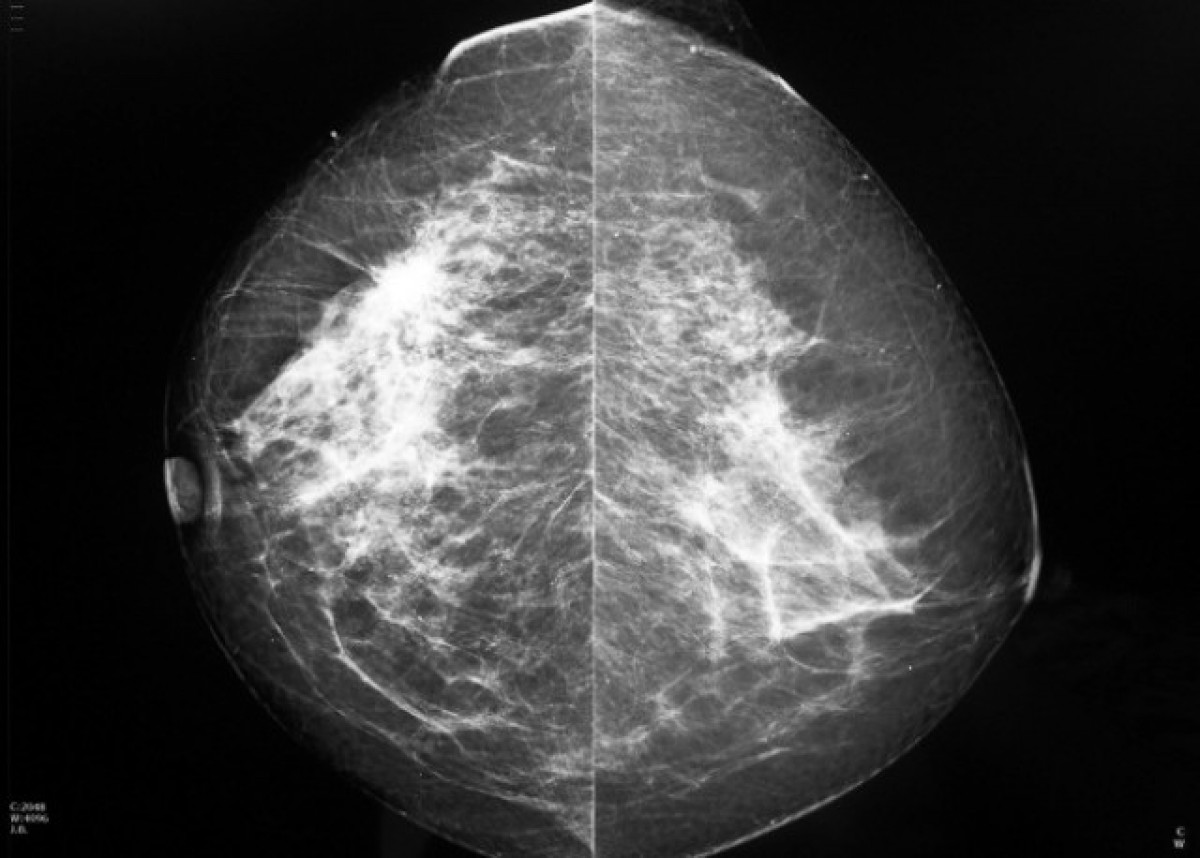

Imatge d'una mamografia.